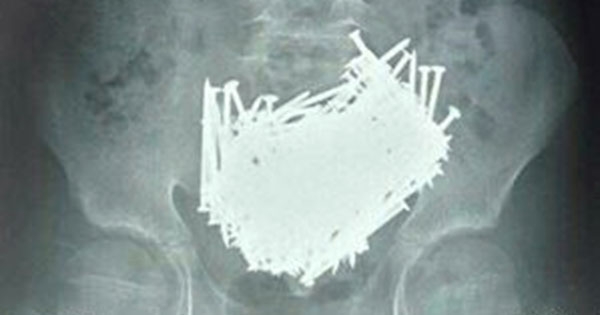

▼醫生馬上就替這位少年進行腹部掃描,結果居然發現一堆像是釘子的物品,想當然地立刻就開始手術。可怕的掃瞄圖片若不知情的人還以為是惡搞,但這是真實男孩肚子中的物品,總共約有200根釘子,還找到一些奇怪的東西,像是牙籤、硬幣、石頭等等,根本不該出現在肚子裡。

▼據說這些物品重量達700克,但還好最後都被取出來了。